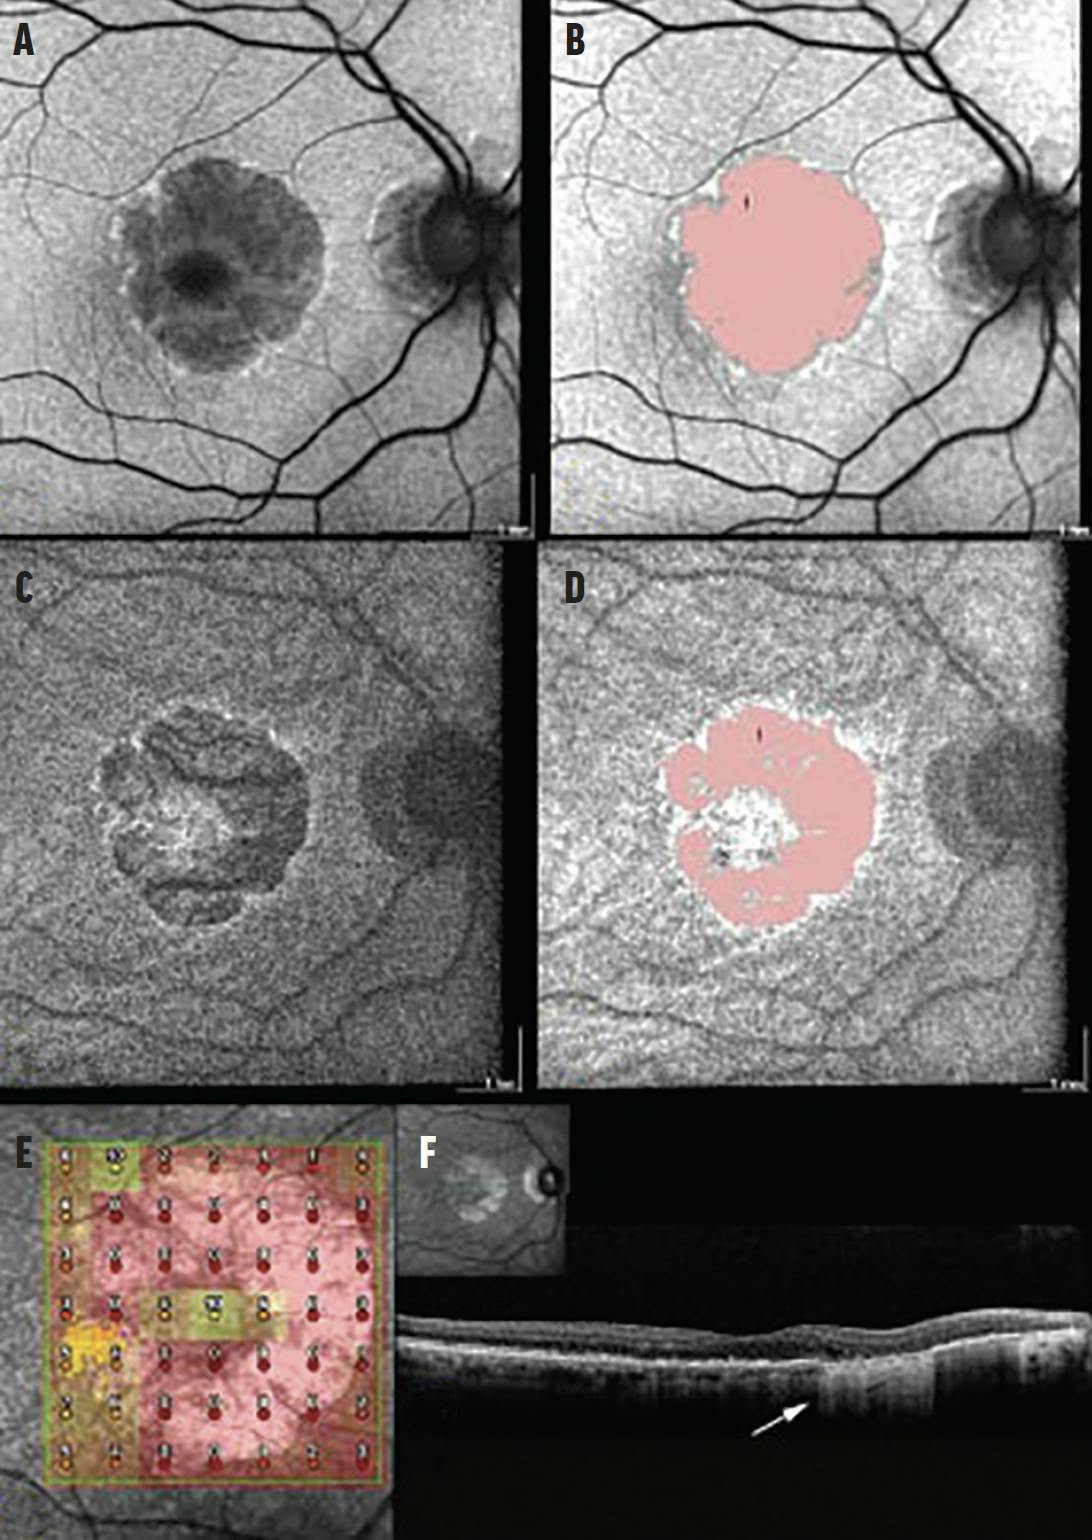

<p>Figure 5. In the FAF of a GA lesion (A), the xanthophyll pigment appears even darker than the dark hypofluorescent zone of GA. In the same FAF image that was processed through automated quantification of the GA lesion (B), the foveal sparing is not detected. In the NIR image (C), the foveal sparing contrasts with the hypofluorescent atrophic lesion. In the same NIR image with automated quantification of the atrophic zone (D), the foveal sparing is detected, allowing a reliable quantification of GA. Microperimetry (E), used to evaluate the macular function, correlates with the foveal sparing detected in the NIR imaging. With OCT imaging (F), the limits of the atrophic zone (cRORA) show the foveal sparing.</p>

Figure 5. In the FAF of a GA lesion (A), the xanthophyll pigment appears even darker than the dark hypofluorescent zone of GA. In the same FAF image that was processed through automated quantification of the GA lesion (B), the foveal sparing is not detected. In the NIR image (C), the foveal sparing contrasts with the hypofluorescent atrophic lesion. In the same NIR image with automated quantification of the atrophic zone (D), the foveal sparing is detected, allowing a reliable quantification of GA. Microperimetry (E), used to evaluate the macular function, correlates with the foveal sparing detected in the NIR imaging. With OCT imaging (F), the limits of the atrophic zone (cRORA) show the foveal sparing.